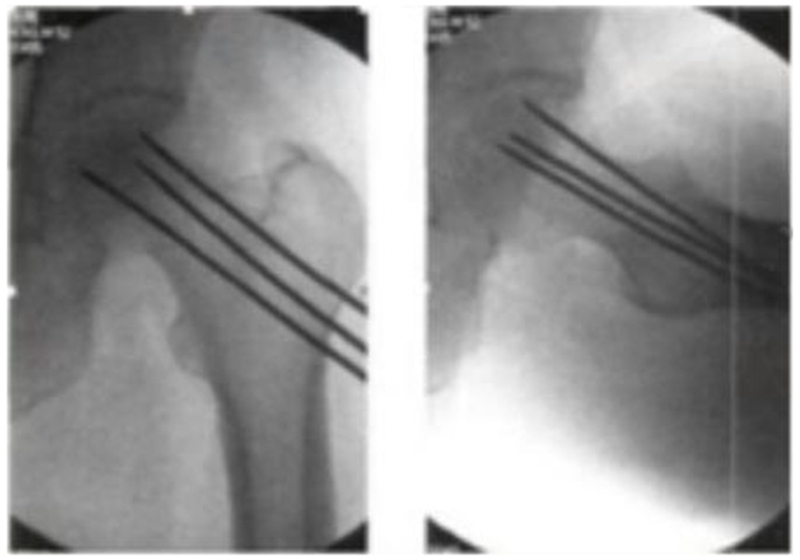

3、多孔细针(Multiple CD,MCD)髓芯减压术

为了克服单孔髓芯减压术的缺点,科学家们进行了改进,采用细针进行多孔道的髓芯减压,通过以直径为3-4mm的克氏针代替传统钻头,进行多方向多孔道的减压MCD和SCD相比,可到达更多的坏死区域,减压更彻底,手术创伤更小。由于对股骨头、股骨颈处结构影响小,保留孔道之间的支撑结构,因此股骨头塌陷、骨折等并发症发生率也更低。

2004年,Mont首次报道多孔径技术对股骨头坏死塌陷前FicatⅠ期患者2年随访,其成功率为80%。2008年,David研究表明,多孔径髓芯减压术组较传统髓芯减压术组,可适应坏死分期更高。文献报道在坏死范围较小者,失败率在14%-25%,坏死范围较大者,失败率达42%-84%。

一项研究显示,多孔径适应证主要限于Ficat分期Ⅰ、Ⅱa和Ⅱb,但也包括一些Ⅲ期的年轻病人,长达11年的随访,163个关节中的108个(66.3%)最后一次随访时被认为是临床上成功的。在108个被认为是临床成功的髋关节中,34个在随访期间出现了额外的塌陷。74个关节(45.4%)被认为达到了放射学和临床成功。

2016年Brown也认为,经皮多孔径随芯减压术(MCD)较传统单孔芯减压术(SCD),有更少软骨损害及转子下骨折及容易操作等优势,但临床疗效相近,不管是SCD还是MCD,在减压后股骨头修复的过程中,骨吸收的速度往往较新骨的形成快,使本薄弱的软骨下骨的机械支撑力进一步减弱从而更易引起股骨头塌陷,塌陷率仍有30%左右,患者仍需拄拐下地或限制活动。